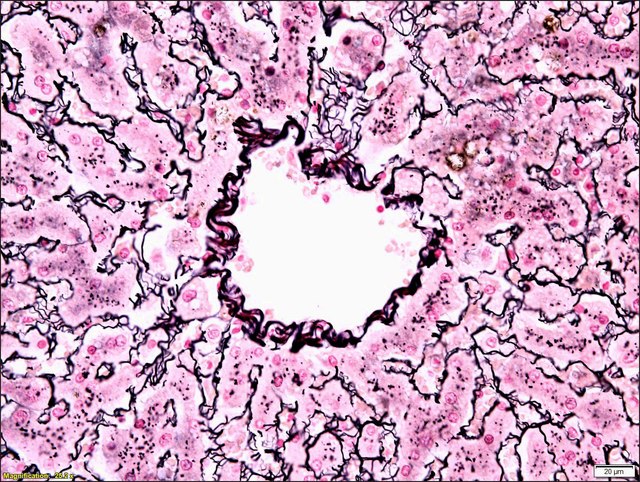

📌 Reticulin Stain

يستهد الياف ال Reticulin

وتظهر باللون الاسود